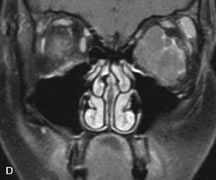

On MRI, uveal melanomas have a typical appearance that helps to differentiate them from other primary and secondary intraocular tumors as well as choroidal detachments. Pigmented melanomas are hyperintense on Tl-weighted images, hypointense on T2-weighted studies, and hyperintense on proton density–weighted examinations (Fig. 24).30,31,50,80–82 These signal characteristics have been attributed to the paramagnetic properties of melanin because of stable free radicals that shorten the T1 and T2 relaxation times. Moderate enhancement is seen on postgadolinium T2-weighted images. Gadolinium-enhanced T1-weighted images are particularly sensitive in detecting choroidal melanomas.83 MRI may be less sensitive in detecting extrascleral extension of tumor than echography performed by an experienced ultrasonographer.84

Fig. 24. A. T1- and (B) T2-weighted MR scans demonstrate a small nodular intraocular mass (arrows) that is very hyperintense on the T1-weighted scan and hypointense on the T2-weighted image. This signal intensity pattern is due to the presence of free radicals within melanin granules. C and D. Postcontrast fat-suppressed T1-weighted scans demonstrate homogeneous intense enhancement of the lesion and no evidence of seleral penetration or optic nerve invasion.